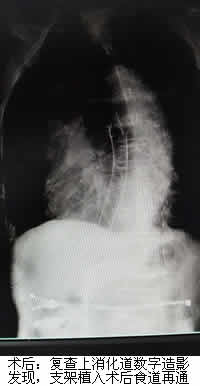

郑老伯今年已81岁高龄,因“进行性吞咽困难1月余”就诊当地医院,诊断结果为晚期食管癌。由于年纪大不宜手术,郑老伯一年内行多次放化疗后仍出现食管肿物进行性增大,原来吃面食现在只能喝水,甚是痛苦。经打听,他们了解到福建医科大学附属第一医院介入科通过一种无创的食道支架植入术可以姑息性治疗晚期食管癌,遂转诊我院。在充分了解病情及完善相关检查后,我院介入科治疗团队为郑老伯进行了这种无创手术,手术很顺利,疗效显著。术后第二天医生告诉老伯可以继续吃面食了,郑老伯非常开心,其家属也相当满意,十分感谢我院陈一平、陈仲武两位专家及其团队。

陈一平、陈仲武副主任医师介绍说,食管癌的最大问题是因食道阻塞而患者无法进食,常规上会以肠或胃造瘘的方式解决患者营养或者排便的问题。但胃造瘘仍无法让患者经口进食,而食道支架,可用以撑开肿瘤阻塞的食道,满足患者经口进食的口欲,使患者的营养得到保障,此外,该手术具有疼痛轻、并发症少等优点,对患者也是巨大的心理安慰。食道支架植入术是晚期食管癌患者实现食道再通的一种有效治疗手段。